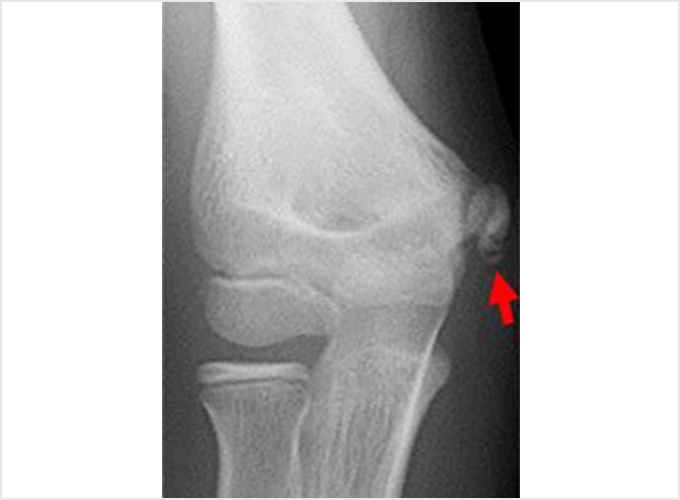

離断性骨軟骨炎(上腕骨小頭障害)

野球肘で最も重症になる障がいの1つです。ひどくなると関節軟骨の一部がはがれて関節ネズミとなったり、肘が変形して動きが悪くなったりします。初期に発見されれば投球禁止で治り、手術はしなくてもすむ場合が多いのですが、末期になると手術が必要となり、手術をしても肘の動きの制限や変形が残ってしまうこともあります。10歳前後で発症することが多いのですが、初期には自覚症状がないことが多く、13-17歳ごろにグラグラになった軟骨がはがれて痛みが出て初めて医療機関を受診されることもよくあります。 手術となった場合には骨の成長の度合い、病変の進行具合、病変の大きさなどにより手術方法が変わります。軟骨が安定している場合には軟骨を固定する手術を行う場合が多いです。軟骨がはがれている場合、病変が小さければ関節鏡を用いてはがれた、あるははがれかけている軟骨を摘出します(図4a)。病変の直径が1㎝以上であれば切開手術で膝の軟骨を病変部に移植します(図4b)。 最近全国各地で少年野球検診が行われるようになりましたが、一番の目的は離断性骨軟骨炎を早期に発見し、重症になる前に治療を行うことなのです。平成28年から多くの医師、理学療法士の協力により名古屋でも行われるようになりました。私も検診に参加し、エコーでのチェックを担当しました。およそ100人に1-2人の割合で発見されました。